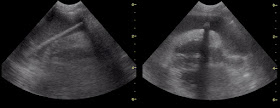

En el estudio ecográfico salta la sorpresa, al apreciarse una estructura lineal en el pericardio del paciente.

ecocardiografia corazon perro

He subido el vídeo, para que lo podáis apreciar de un modo más directo.

En ese momento los dueños recuerdan el episodio del pincho moruno y todo parece indicar que el trozo del palo que se partió ha atravesado el pericardio y ha llegado al corazón.